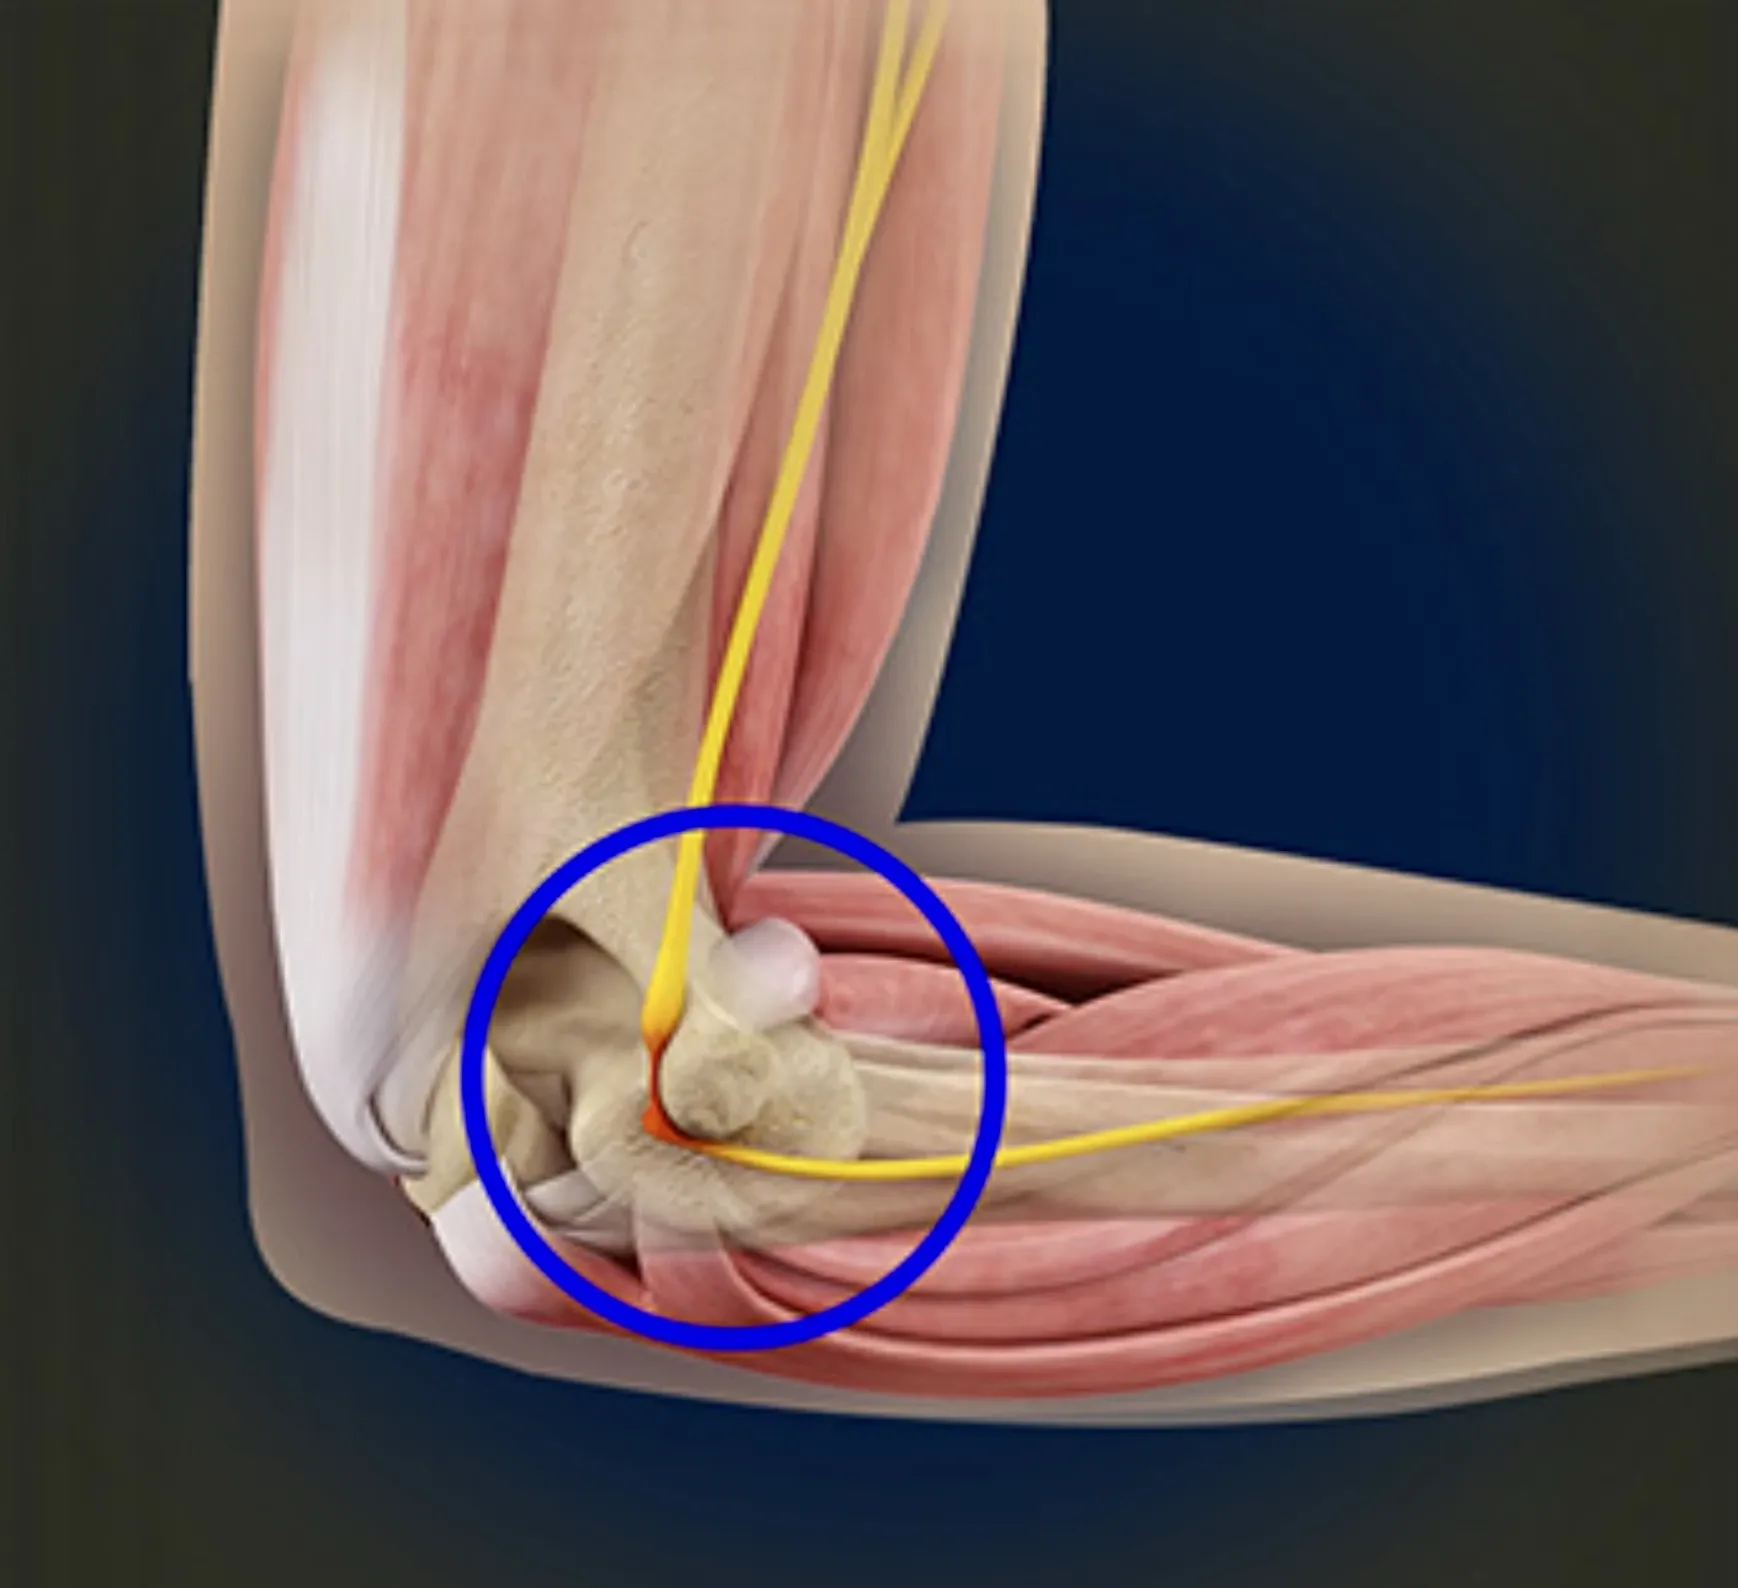

Cubital tunnel syndroom

Omschrijving

Bij dit syndroom komt er te veel druk op de nervus ulnaris aan de binnenzijde van de elleboog.

Klachten

- Tintelingen of doofheid in pink en ringvinger

- Verergering klachten bij leunen op de elleboog of langdurig plooien (telefoon, slapen)

- Soms krachtsverlies /onhandigheid in de hand

Behandeling

- Aanpassen van houding en activiteiten

- Nachtspalk om buigen van de elleboog te vermijden

- Bij ernstige of blijvende klachten: operatie om druk van de zenuw weg te nemen; soms wordt de zenuw verplaatst naar de voorzijde van de elleboog

Nabehandeling

Korte immobilisatie van de elleboog, na aantal dagen mobiliseren op geleide van pijn. Het herstel van de zenuw kan enkele maanden duren en hangt af van de ernst van het letsel.